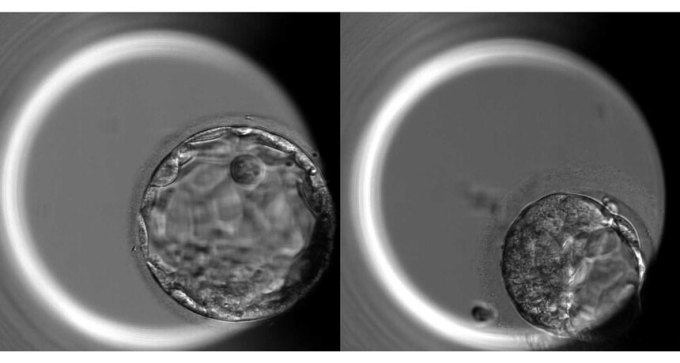

In a first, human embryos edited to explore gene function

In groundbreaking research, CRISPR/Cas9 used to study human development for the first time.